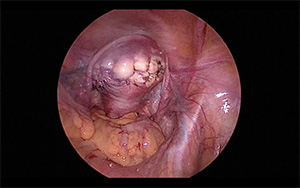

자궁근종 수술은 여러 가지 방법으로 진행될 수 있습니다. 전신 마취 또는 국소 마취를 한 후, 복부나 질을 통해 접근하여 근종을 제거합니다. 개복술인 경우 1~2주 정도의 입원과 한달 정도의 회복 기간이 필요하고, 자궁근종 색전술은 1~3일 정도의 짧은 입원과 회복 기간도 짧습니다. 자궁근종 수술의 비용은 병원이나 지역에 따라 차이가 있으며, 평균적으로 수백만 원에서 천만 원 이상이 소요될 수 있습니다. 이때, 보험 적용 여부도 중요한 사항이므로 미리 확인하는 것이 좋습니다.